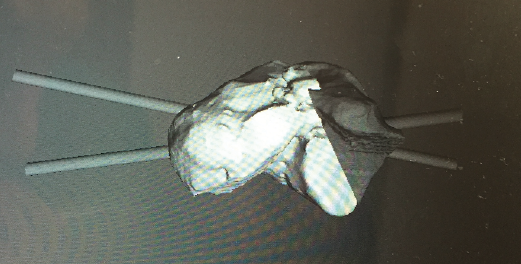

Figura 2. Modelo 3D del defecto del astrágalo.

- Obtención de la forma real del defecto combinando el astrágalo con una imagen especular del astrágalo contralateral (Figura 2).

- Impresión 3D del defecto del astrágalo y guía para la colocación de las agujas (Figura 3).